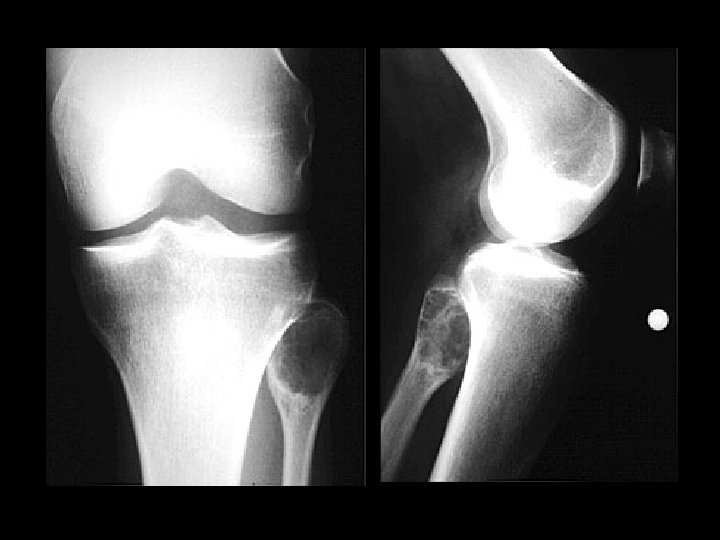

Pellegrini-Stieda disease • • Findings: – Linear ossific density adjacent to the medial femoral condyle Calcification or ossification of the MCL at its insertion site Sequela of previous injury NOT acute, usually not the site of pain

Aneurysmal bone cyst • Findings: – Lucent end of bone lesion in the proximal tibia – Slightly expansile, mild periosteal reaction – Fluid-fluid level on MRI • ddx: – Giant cell tumor – Unicameral bone cyst – Fibrous dysplasia – Chondroblastoma (rare)